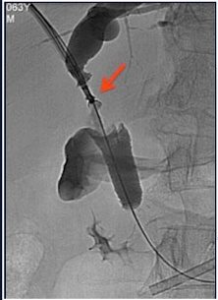

Un campo di applicazione in radiologia interventistica è, ad esempio, la biopsia endobiliare,

ovvero la biopsia eseguita in un dotto biliare mediante l’utilizzo di un’apposita pinza,

introdotta per via percutanea